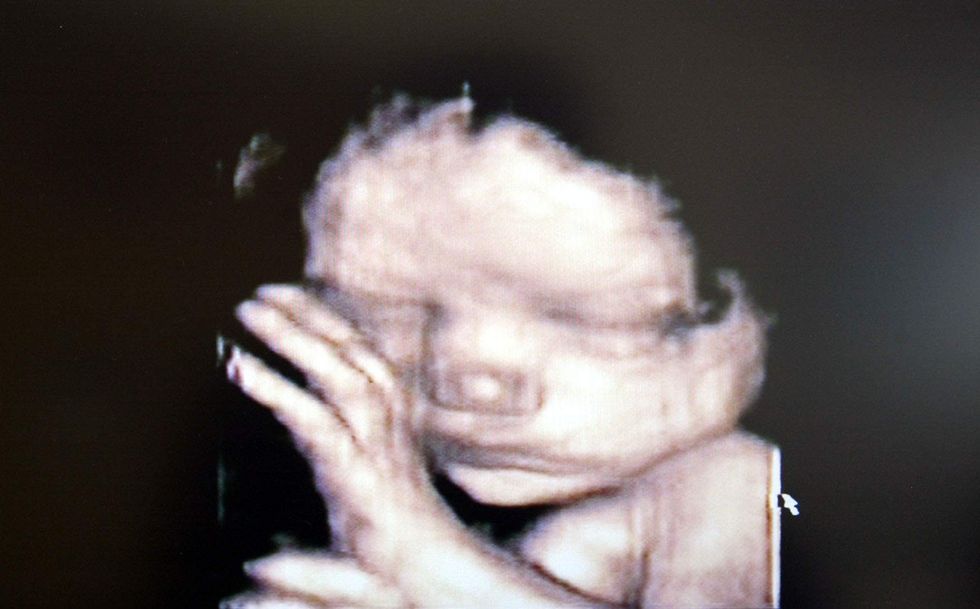

The advancements of science and technology have been influential for today’s pro-lifers. The younger generation grew up with the idea that your first “baby picture” is an ultrasound, something that has made a profound difference to how they see life in the womb.